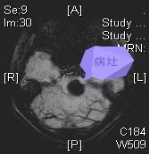

33岁的陈女士(化名)近来总觉得右半边身体麻木无力,走路不稳、头痛头晕,来到我院神经医学中心求诊。通过磁共振检查,发现其脑干偏左侧,有个海绵状血管瘤,同时还伴有出血。

术前检查:海绵状血管瘤处于脑干偏左侧